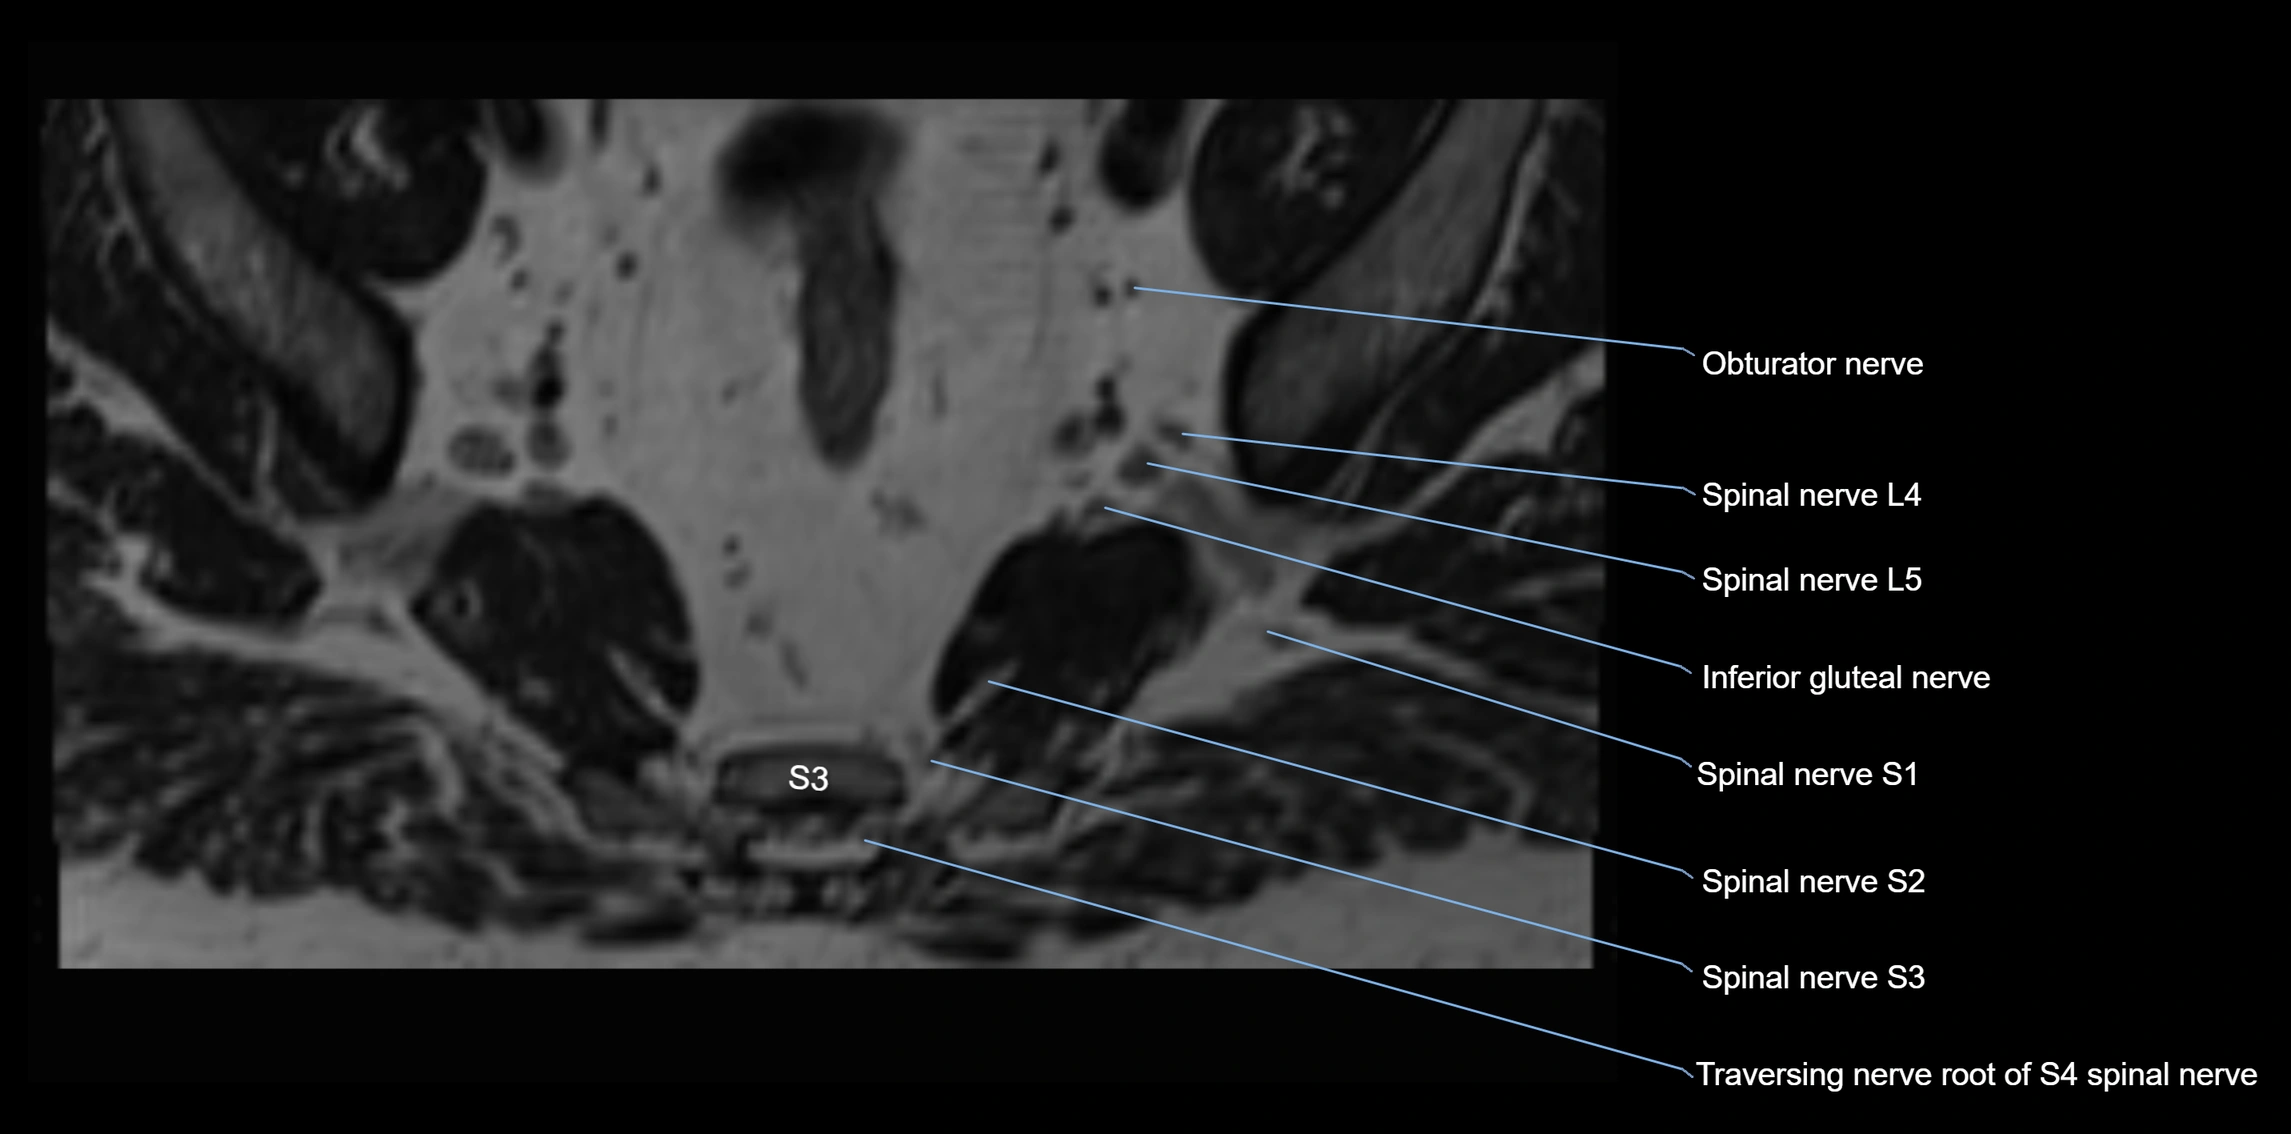

MRI Appearance

T1-weighted images:

• Nerve appears as a very thin low-to-intermediate signal intensity structure

• Surrounded by bright fat, aiding visualization

T2-weighted images:

• Nerve shows intermediate to mildly hyperintense signal compared to muscle

• Pathological involvement appears brighter

STIR (Short Tau Inversion Recovery):

• Normal nerve appears dark

• Inflamed or entrapped nerve appears bright hyperintense

T1 Fat-Sat Post-Contrast:

• Normal nerve enhances minimally

• Pathologic nerve (neuritis, entrapment, tumor infiltration) shows focal or diffuse enhancement

3D T2 SPACE / CISS:

• Nerve appears intermediate to mildly hyperintense compared to muscle

• Surrounded by bright fat or CSF, improving visualization

• Best sequence for mapping small pelvic nerves such as the anococcygeal

MRI image

image